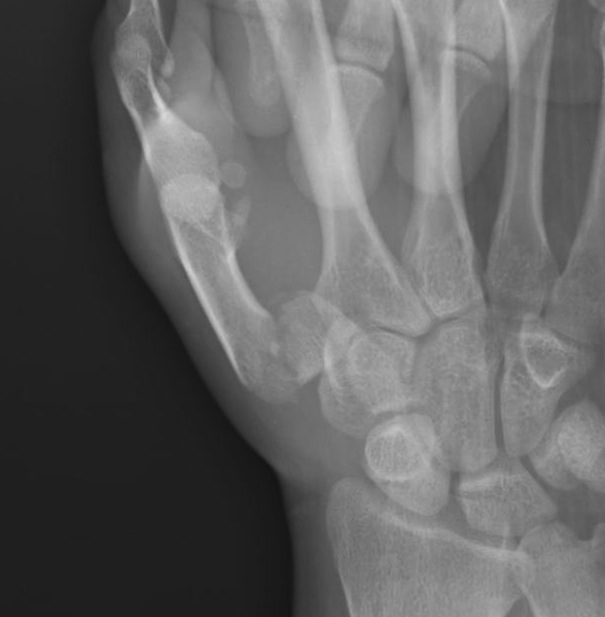

B. Rolando Fracture

Fracture

- 2 small intra-articular fragments

- poor prognosis

Operative management

Indications

Displacement

Technique

Dorsal approach

- protect superficial radial nerves

- between APL / EPB and EPL

- attempt to anatomically reduce and fix with plate